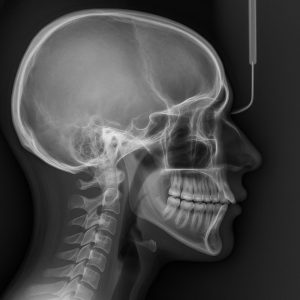

Telerendgen

profilni snimak

Automatsko prepoznavanje cefalometrijskih tačaka i mekih tkiva na Telerendgen profilnom snimku.